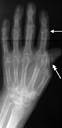

4. Фалангиты. Поражение коротких трубчатых| костей, которое выявляется|проявляются| в виде оститов|, остеомиелитов|, периоститов|, остеохондритов|. Рентгенологически чаще определяются периостальные наслоения и склерозирование| костной структуры.

Поражение костей при позднем врожденном сифилисе наблюдается в 1-2 и даже 4-5 лет и в более позднем возрасте. Определяется|проявляется| в виде множественных периоститов| и оститов|. Наблюдается деформация костей (например: т. наз|. саблевидные голени).